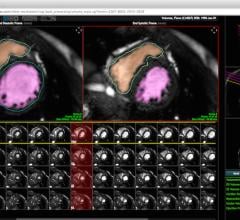

ScImage announced the immediate availability and deployment of updated quantification metrics based on guidelines published jointly in January 2015 by the American Society of Echocardiography (ASE) and the European Association of Cardiovascular Imaging (EACVI).

Heart Imaging Technologies announced the release of Precession, a cardiac magnetic resonance solution which allows viewing, analysis and reporting all within a standard web browser.